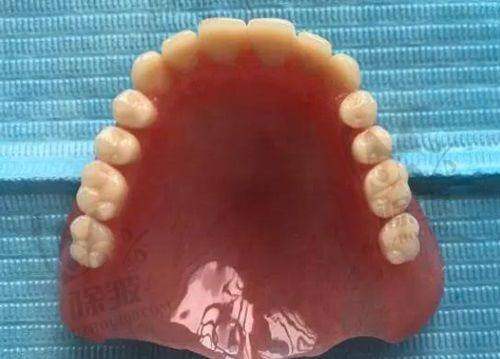

牙贴面是一种覆盖部分牙面的瓷或树脂等材料的修复体。它主要通过粘结技术,将人工修复体固定在患牙表面,以修复牙体的正常形态或改善其色泽。牙贴面的优点有特别多,首先它的磨除牙体组织少,对牙齿的损伤相对较小。与传统的烤瓷牙相比,牙贴面只需要磨除少量的牙齿表面组织,就能达到良好的美容成效。其次,牙贴面的美观度高,尤其是全瓷贴面,它的颜色和透明度与天然牙齿非常接近,几乎可以达到以假乱真的成效。另外,牙贴面的使用寿命也比较长,如果保养得当,可以使用10年甚至更长时间。不过,牙贴面也有一些缺点。比如它的价格相对较高,尤其是进口全瓷贴面;而且牙贴面的边缘可能会出现微渗漏的情况,导致牙齿出现继发龋等问题。所以,在做牙贴面之前,患者一定要充分了解牙贴面的优缺点,根据自己的实际情况做出选择。